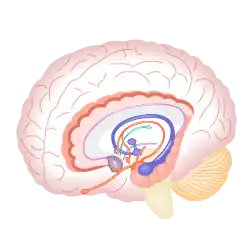

Addiction

Drug addiction may be regarded as a disease of the brain's reward system.[201] This system, closely related to the system of emotional arousal, is located predominantly in the limbic structures of the brain. There are several groups of substances that activate the reward system and they may result in addiction, which in humans is a chronic, recurrent disease, characterized by absolute dominance of drug-seeking behavior.[202] Drug abuse affects the prefrontal cortex, a brain region also involved in the reward system, diminishing or impairing the use of self control or judgment in addicts.[203] Dopamine is the primary neurotransmitter involved in the reward mechanism of the limbic system.[204]

Cocaine is a short-acting SNDRI that also exerts auxiliary pharmacological actions on other receptors.[4] Cocaine is a relatively "balanced" inhibitor, although facilitation of dopaminergic neurotransmission is what has been linked to the reinforcing and addictive effects. Cocaine users may experience symptoms of extreme fatigue, decreased mood, and a "crash" following the original euphoria of the drug; subsequent to the crash, users begin to crave for more.[205] In addition, cocaine has some serious limitations in terms of its cardiotoxicity due to its local anesthetic activity.[206] Thousands of cocaine users are admitted to emergency units in the USA every year because of this; thus, development of safer substitute medications for cocaine abuse could potentially have significant benefits for public health.[207]